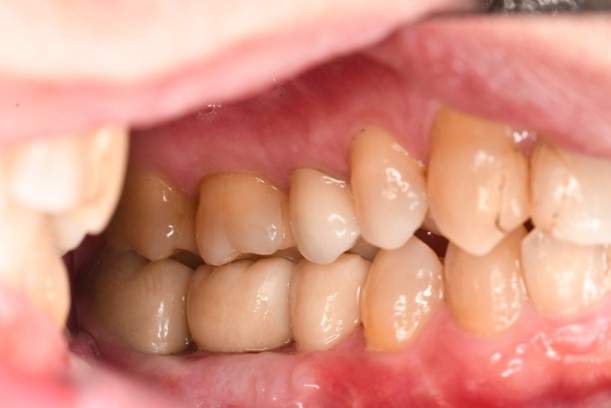

口腔内写真

- Befor

- After

| 治療方針 | 左上7番は昔他院で被せものをしており、被せものの中が歯ぐきの中まで虫歯になっていたため抜歯せざるを得ない状態だった。抜歯と同時に骨造成を行い、骨が出来るまで4ヵ月待ってからインプラントを埋入した。 ※2ポンティック・・・歯のない部分を補うダミーの歯。 |

| 担当者所見 | 元々金属の被せものが多く入っていたため、2次カリエス※3が多かった。今回は金属ではなく、ジルコニアを使用し、2次カリエスにならないよう、患者様にはブラッシング指導とメンテナンスの重要性をお伝えした。 ※3二次カリエス・・・詰め物や被せものを入れた歯が虫歯になること。 |